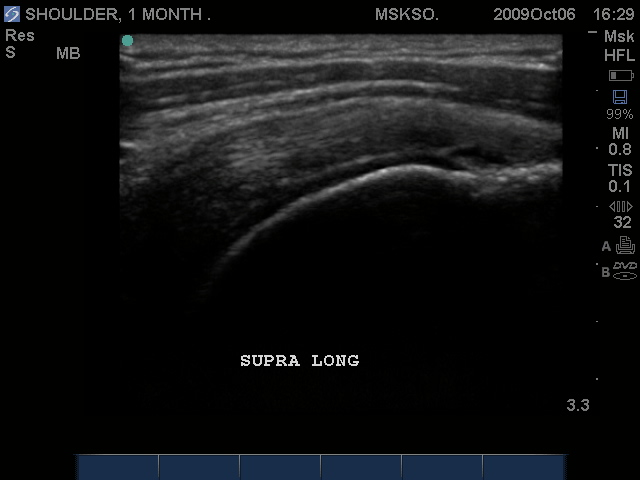

Anterior movement of the probe from the prior image shows beginning of cortical irregularities seen at the lateral Greater Tuberosity

Anterior Greater Tuberosity imaged as a more pronounced curved cortical margin. This area of the insertion is truly Supraspinatus with no Infraspinatus merger. Here we see more cortical irregularity deeper into the cortex.